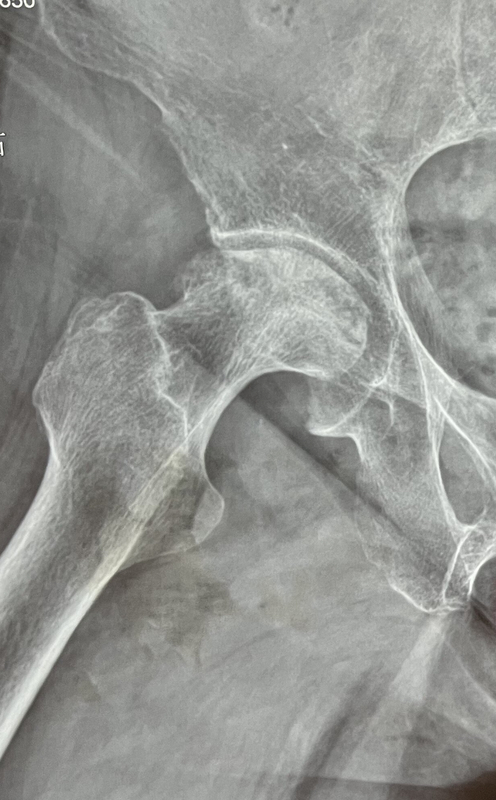

患者70多岁,股骨头坏死,股骨头塌陷变形,疼痛明显,活动困难手术前使用机器人辅助规划设计手术方案,选择适合患者的假体型号并设计最佳假体安放位置手术采用微创小切口手术技术,切口长度8-9厘米,有限且足够的显露可以明显减小手术创伤,有效保护肌肉等软组织,减轻手术损伤会直接降低手术后患者疼痛不适的感觉手术中机器人辅助设备注册一次完成,不会因为切口小而影响手术注册的过程手术时间一小时左右,出血少,患者手术后疼痛很轻,恢复快手术后一个月复查,患者已经不用扶拐行走自如。伤口愈合很好,完美小切口在合适的患者中,髋关节置换手术可以使用微创小切口的手术技术,即使需要机器人辅助注册患者骨性标志的情况下,一样可以使用微创小切口的手术技术,给患者带来创伤小,假体位置精准,疼痛轻,恢复快的优点。